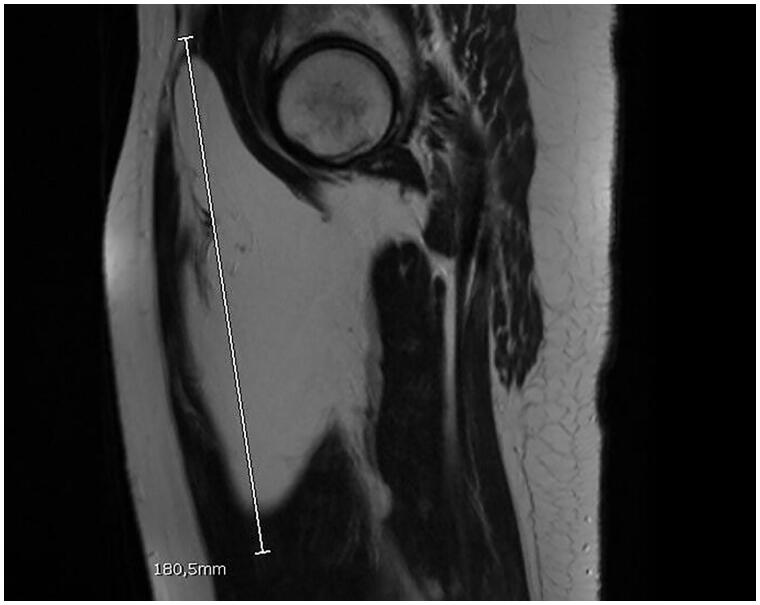

Figure 2.

Sagittal section of MRI of lipoma.

The cross section of the tumor size was 10 cm × 8 cm with an 18 cm long axis length.